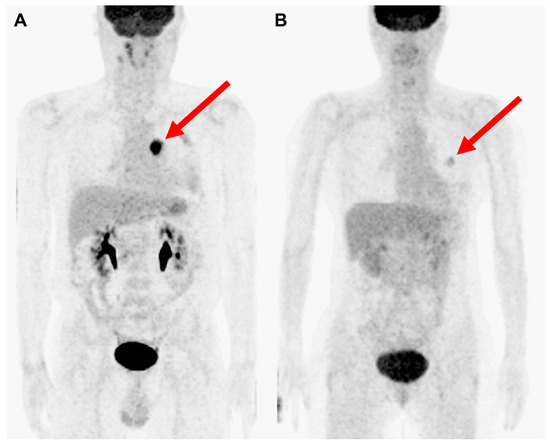

2.2. FDG PET/CT Acquisition and Analysis